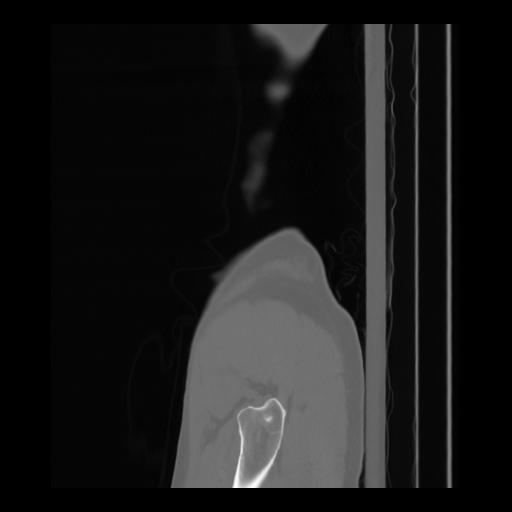

36 CUERPO,CE,Sagittal,3.000,CUERPO,Sagittal,